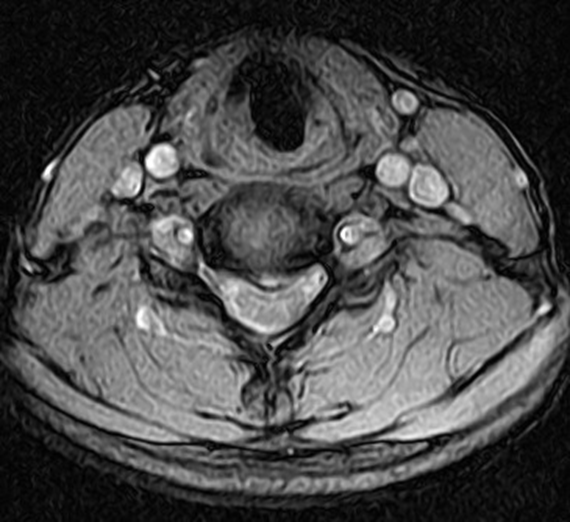

Cervical Disc Herniation MRI

Cervical Disc Herniation MRI Acupuncture For Herniated Cervical Disc Acupuncture successfully reduces inflammation and pain caused by a herniated disc. Research has already confirmed that acupuncture can help back pain and a new study. Researchers from hannan district peoples hospital foun d that acupuncture combined with moxibustion had a 90% success rate in treating herniated discs in the lower back. A 2021 study assessed acupuncture for the treatment of. Acupuncture For Herniated Cervical Disc.